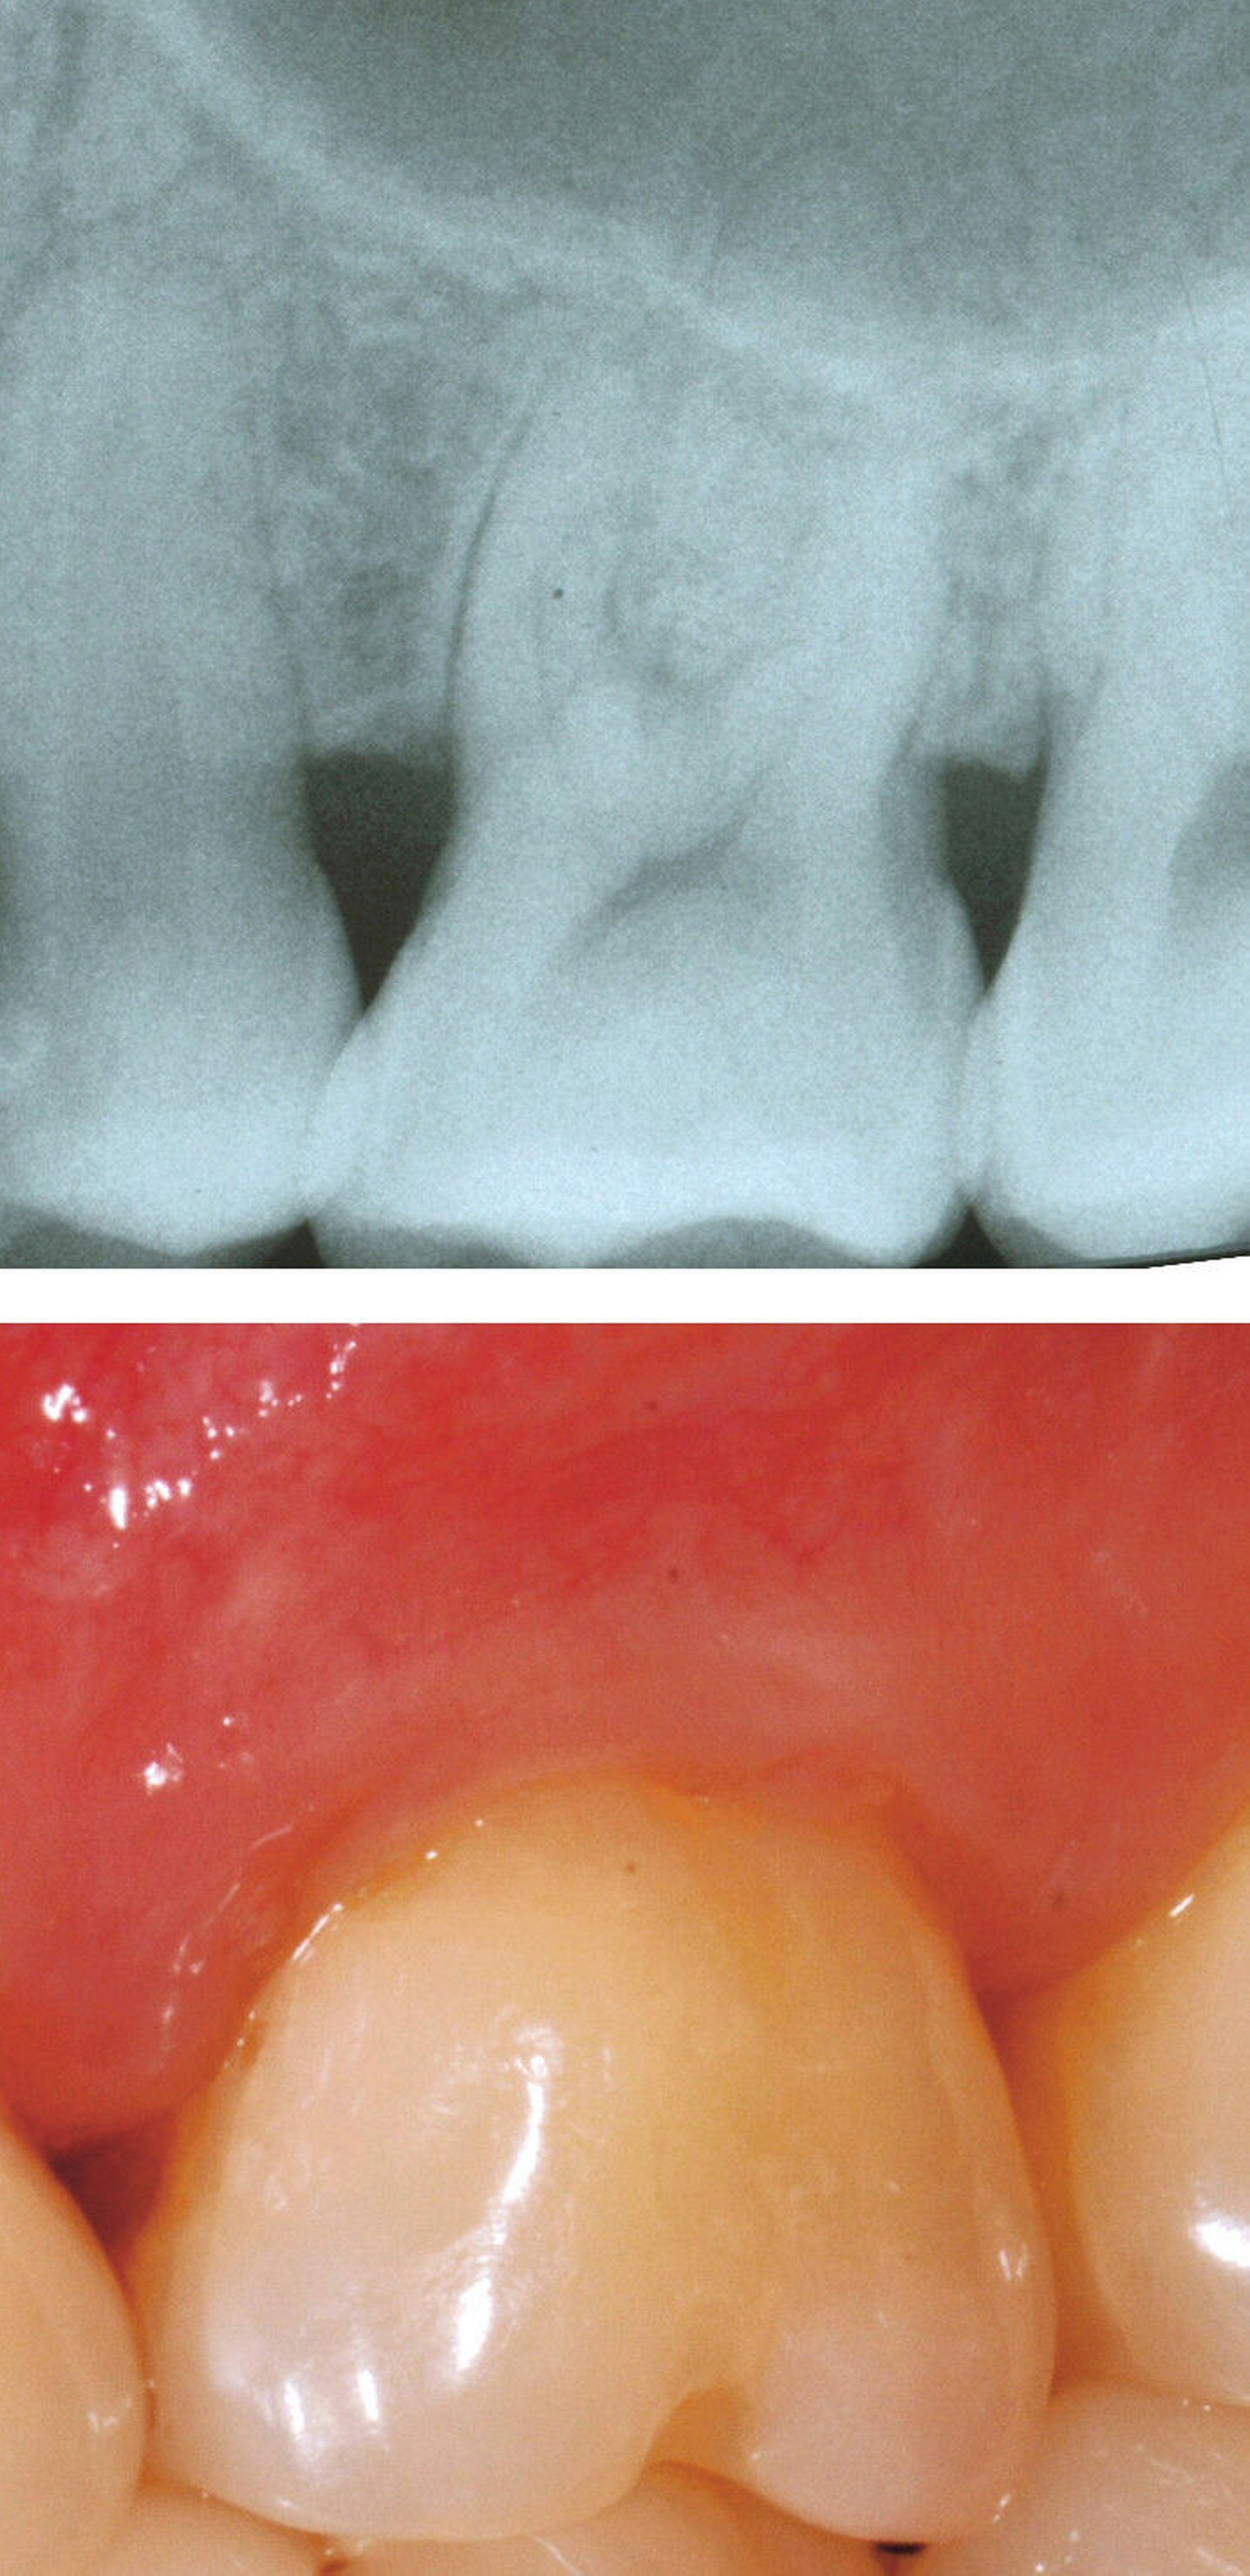

Systemische Faktoren, die den Erfolg regenerativer Maßnahmen beeinflussen können, sind beispielsweise ein unkontrollierter Diabetes oder eine eingeschränkte Immunabwehr. Verhaltensfaktoren wie Rauchen, unzureichende Mundhygiene und mangelnde Adhärenz müssen ebenfalls bei der Fallauswahl berücksichtigt werden. Zu den anatomischen beziehungsweise Defektfaktoren, die sich einigen Studien zufolge und nach Expertenkonsens negativ auf die Erfolgsaussichten einer regenerativen Furkationstherapie auswirken können, werden gezählt: ein erschwerter Zugang zum Operationsbereich, ein approximales Knochenniveau, das sich auf derselben Höhe oder sogar apikal des Furkationsdaches befindet, ein kurzer Wurzelstamm, ein enger Abstand zwischen den Wurzeln mit erschwerter Instrumentierung, eine deutlich erhöhte Zahnbeweglichkeit, ein dünner gingivaler Phänotyp, wenig keratinisiertes Gewebe, die Nähe eines Restaurationsrandes zum Furkationseingang und das Vorliegen einer gingivalen Rezession im Furkationsbereich.

Ein adäquater Zugang zum Operationsbereich und auch für die zukünftigen Mundhygienemaßnahmen ist äußerst wichtig. Molaren mit Grad-II-Furkationsdefekten (mandibulär und bukkal maxillär) sind Kandidaten, die für ein regeneratives Verfahren infrage kommen. Basierend auf der verfügbaren Evidenz sind interdentale Grad-II-Furkationsdefekte an Oberkiefermolaren deutlich weniger geeignet, höchstwahrscheinlich aufgrund des eingeschränkten Zugangs. Weitere lokale Charakteristika können Auswirkungen auf die Ergebnisse der regenerativen Furkationschirurgie haben. Zum Beispiel können ein dickerer Phänotyp und das Fehlen einer Weichgeweberezession die Heilung nach GTR-Verfahren positiv beeinflussen. Günstigere Ergebnisse sind an Stellen zu erwarten, an denen das verbleibende approximale Knochenniveau koronal zum Eingang beziehungsweise zum Dach des Furkationsdefekts liegt, verglichen mit solchen, bei denen das approximale Knochenniveau auf der Höhe oder apikal des Furkationseingangs liegt. Ein enger interradikulärer Abstand kann eine gründliche Defektinstrumentierung beeinträchtigen. Das Vorhandensein einer Wurzelkanalfüllung ist nicht per se eine Kontraindikation für die Furkationsregeneration – vorausgesetzt, es gibt keine Anzeichen für apikale pathologische Veränderungen.